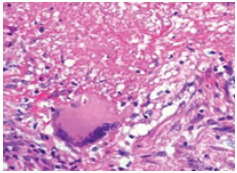

Figure 2:(HE x 400) Tuberculosis showing lymphocytes, epithelioid cells, giant Langhans cells and caseous necrosis.

This is a 10 years old patient admitted for nasal ulceration. The clinical history dates back three months to the insidious installation of bilateral nasal obstruction associated with fetid purulent rhinorrhea. In these antecedents no notion of tuberculous contagion was noted, a BCG vaccination scar was found on the left arm. The HIV status was negative, and we did not note any family history of nasal tuberculosis. At admission, the patient had a good general condition. The rhinological examination noted a budding ulcerous swelling (Figure 1) of the nasal pyramid. Otoscopy revealed polyps filling the two external auditory canals. The remainder of the clinical examination found a dorsal kyphoscoliosis. At the end of this physical examination, we performed a thoracoabdominal computed tomography that objectified a Pott’s disease. Chest X-ray revealed poorly heterogeneous opacities of the left lung associated with ipsilateral pleuritis. The blood count showed a hypochromic microcytic anemia with thrombocytosis. Tuberculin intradermal reaction was phlyctenular at 15mm and anatomopathology of the cutaneous biopsy of the nasal pyramid revealed gigantocellular follicles with caseous necrosis indicating tuberculosis (Figure 2). We concluded that nasal tuberculosis was multifocal tuberculosis. The patient received a six-month antituberculous treatment with the two months regimen of Rifampicin + Isoniazid + Pyrazinamide + Ethambutol and four months Rifampicin + Isoniazid. We noted a net regression of the lesions at four months after treatment (Figure 3). Any recurrence after one year.

The diagnosis of tuberculosis was based in our case on histopathological examination after biopsy revealing a gigantocellular granuloma with caseous necrosis. It allowed making the diagnosis. The orientative elements have been reported it is the tuberculin intradermal reaction which was positive at 15mm. A definitive diagnosis is made by isolating tubercle bacilli from tissue samples obtained by biopsy or surgery [1]. This diagnosis can be carried out as in our case on the histological aspect highlighting a Langhans giant cell epithelioid granuloma [5].